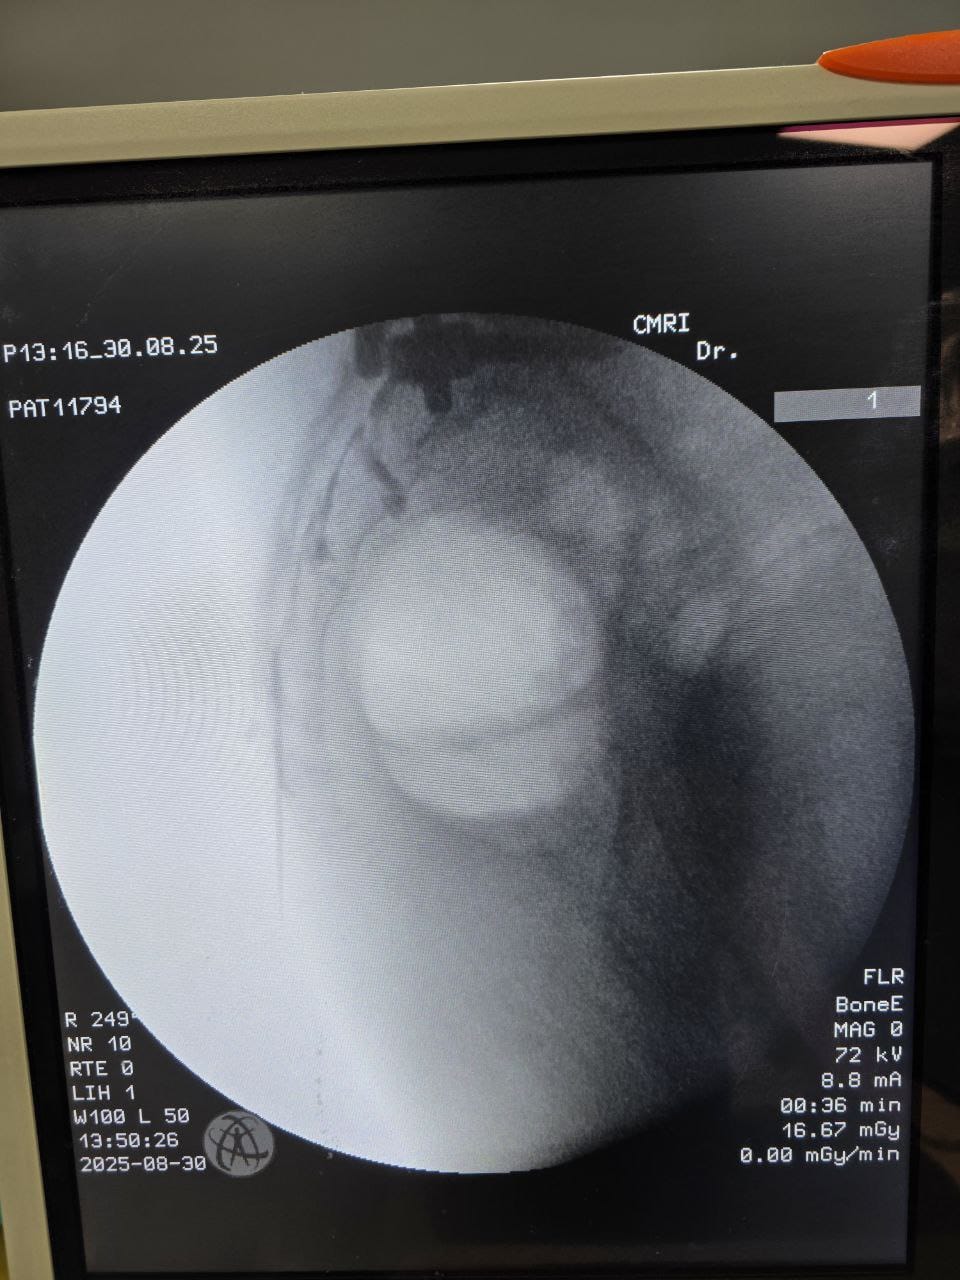

Procedures